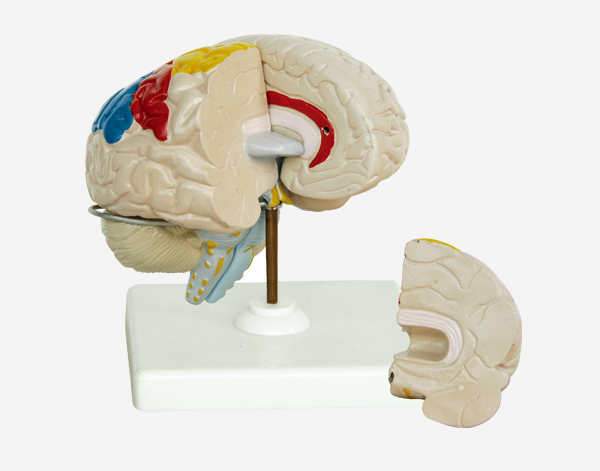

Human Brain With Arteries

Model of Human Brain With Arteries

This model facilitates the medical students to get a correct understanding of the external features of the brain and its arte

rial supply as a whole,as well as the relations between their component portions.External features of the brain:cerebral

hemisphere,brain stem,cerebellum.The arterial supply of the bra inaources,vertebral,internal carotid arteries,arteria supply of the

cerebellum and cerebrum.Made of PVC and can be separated into 7parts,on base.Size(cm):17x17x13